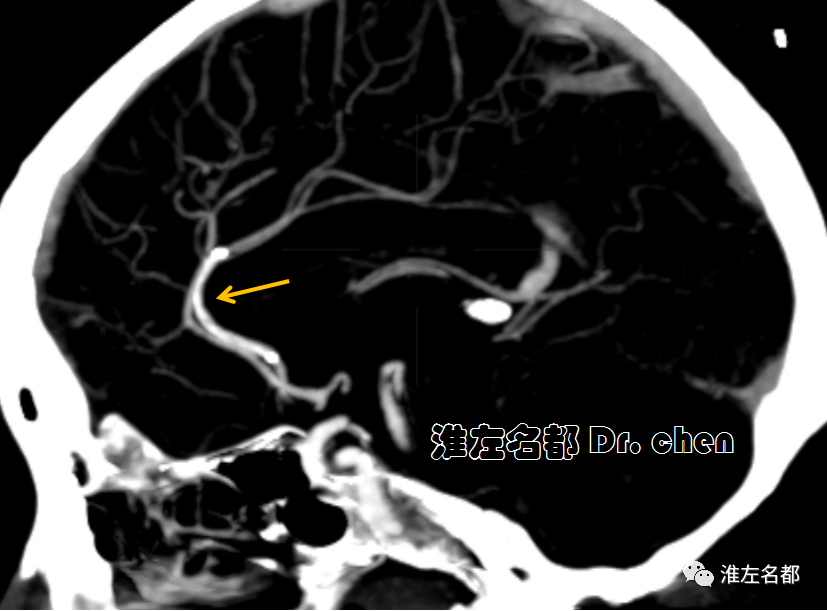

△头颅CTA:左侧大脑前动脉A2段远端闭塞(橙箭)。

△颅脑CTA:左侧大脑前动脉A3段狭窄(橙箭),但前向血流可。

△颅脑CTA:左侧大脑前动脉管腔通畅,未见明显狭窄。